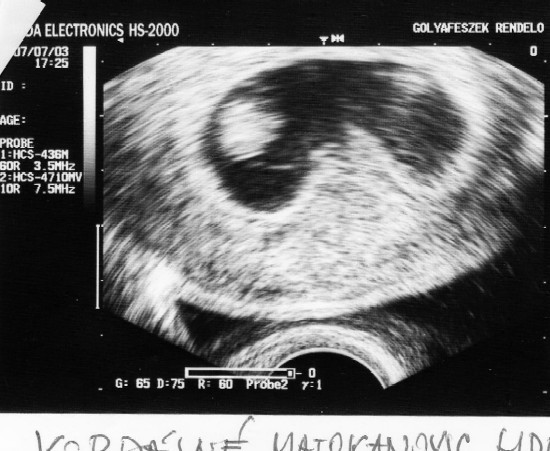

Szuper hír, gratulálok! Jól elbújt az első teszten!